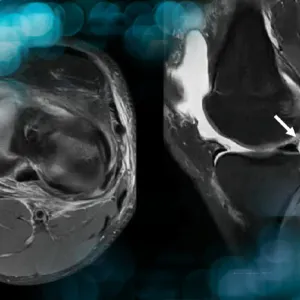

The proper management of medial meniscus ramp lesions in the context of anterior cruciate ligament (ACL) reconstruction depends on accurate diagnosis. It is essential to identify these lesions on preoperative MRI and to systematically complement imaging with arthroscopic exploration of the posteromedial compartment of the knee.